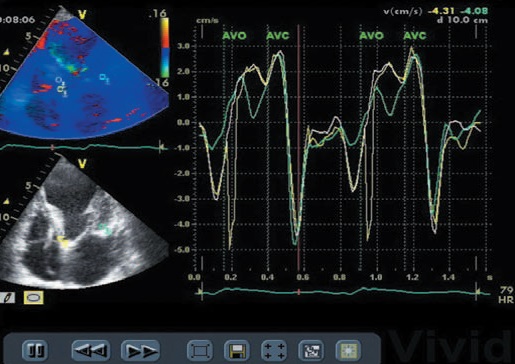

การตรวจหัวใจด้วยคลื่นเสียงสะท้อนระบบ 3 มิติ (3-D Echocardiography) เป็นวิธีการตรวจหัวใจโดยใช้คลื่นเสียงสะท้อนในระบบ 3 มิติ เพื่อการวินิจฉัยโรค รูปที่ได้จะมีความชัดและความลึกแบบ 3 มิติชัดเจนกว่าการตรวจด้วยเครื่องระบบ 2 มิติแบบเก่า

• โครงสร้างและความสามารถในการบีบตัวของหัวใจ